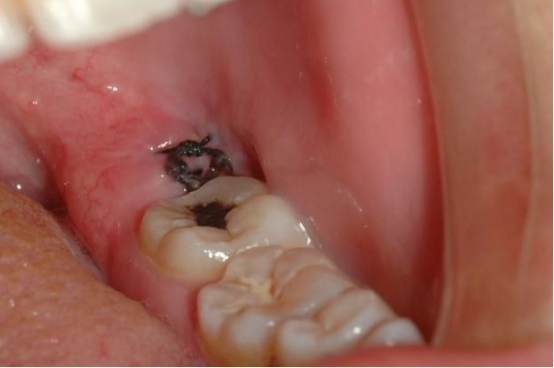

(4)第二磨牙龋坏:向前倾斜的阻生智齿,因经常在邻牙间积存食物,易发生邻牙(下第二磨牙)龋坏。这种龋坏因不在拾面上而不易被发觉,一旦发生疼痛(急性牙髓炎),牙冠常已被严重破坏。即使进行充填治疗,宜难长久保存。下第二磨牙缺失后对咀嚼功能影响较大,用假牙修复亦有困难。